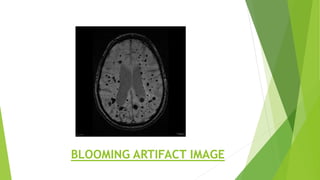

BLOOMING ARTIFACTS

Blooming artifacts is a susceptibility artifact encountered on

some MRI sequences in the presence of paramagnetic substance

that affect the local magnetic milieux. Most affected sequences

are T2*, and in many instances they are designed to exploit this

phenomenon to make certain pathologies more conspicuous. As

such although

it is artifact, it is used deliberately to improve detection of

certain small lesion, much as the T1 shortening effect of low

concentration gadolinium are used to detect contrast

enhancement.

The term “blooming” refers to the fact that lesions appear larger

than they actually are.

BLOOMING ARTIFACT IMAGE